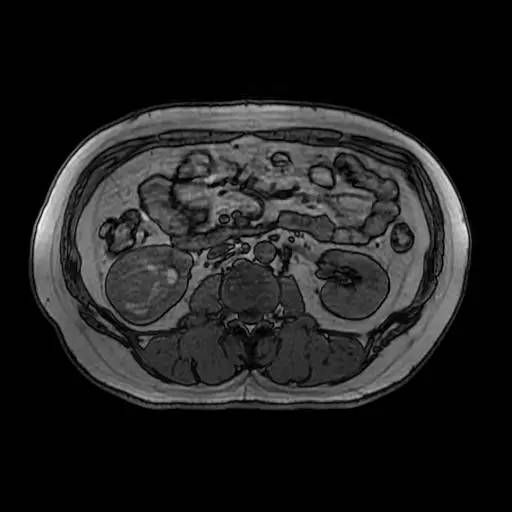

右肾中下部见类圆形约52*49*59毫米类圆形短和稍长T1、短和长T2异常信号肿块,可见假包膜,DWI呈晕环结节状稍高和稍低信号,反相位图像病变信号未见异常减低;皮质期病变未见异常强化,髓质期及延迟期持续轻度强化;病变内小部分区域未见强化。所见肝胆、胰腺、脾脏及双侧肾上腺未见异常,肝门、肾门及所见腹膜后未见异常肿大淋巴结影。

影像诊断:右肾中下部少血供肿块伴出血、坏死和囊变,考虑:恶性肿瘤,以肾癌(非透明细胞癌)可能性最大,不能完全除外表现不典型的血管平滑肌脂肪瘤。